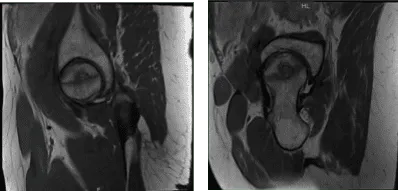

Presentó resultados de resonancia magnética en ambas caderas que mostraron tendinosis común leve en el isquiotibial con una pequeña rotura intrasustancial y edema circundante en la tuberosidad isquial. Necrosis avascular extensa de la cabeza femoral derecha. Cambios degenerativos en la parte baja de la columna lumbar de su cadera izquierda.

Necrosis avascular extensa que afecta la mayor parte de la cabeza femoral derecha y edema de médula ósea circundante que se extiende hasta el cuello femoral. La línea de fractura subcondral en forma de media luna se observa medialmente sin colapso o fragmentación articular.

Existen cambios osteofíticos leves en la articulación acetabular femoral derecha y un derrame articular moderado. Tendinosis leve del gluteo mínimo sin desgarro, para la cadera derecha.

Resonancia magnética Sin contraste en la cadera izquierda

Resonancia magnética Sin contraste en la cadera derecha